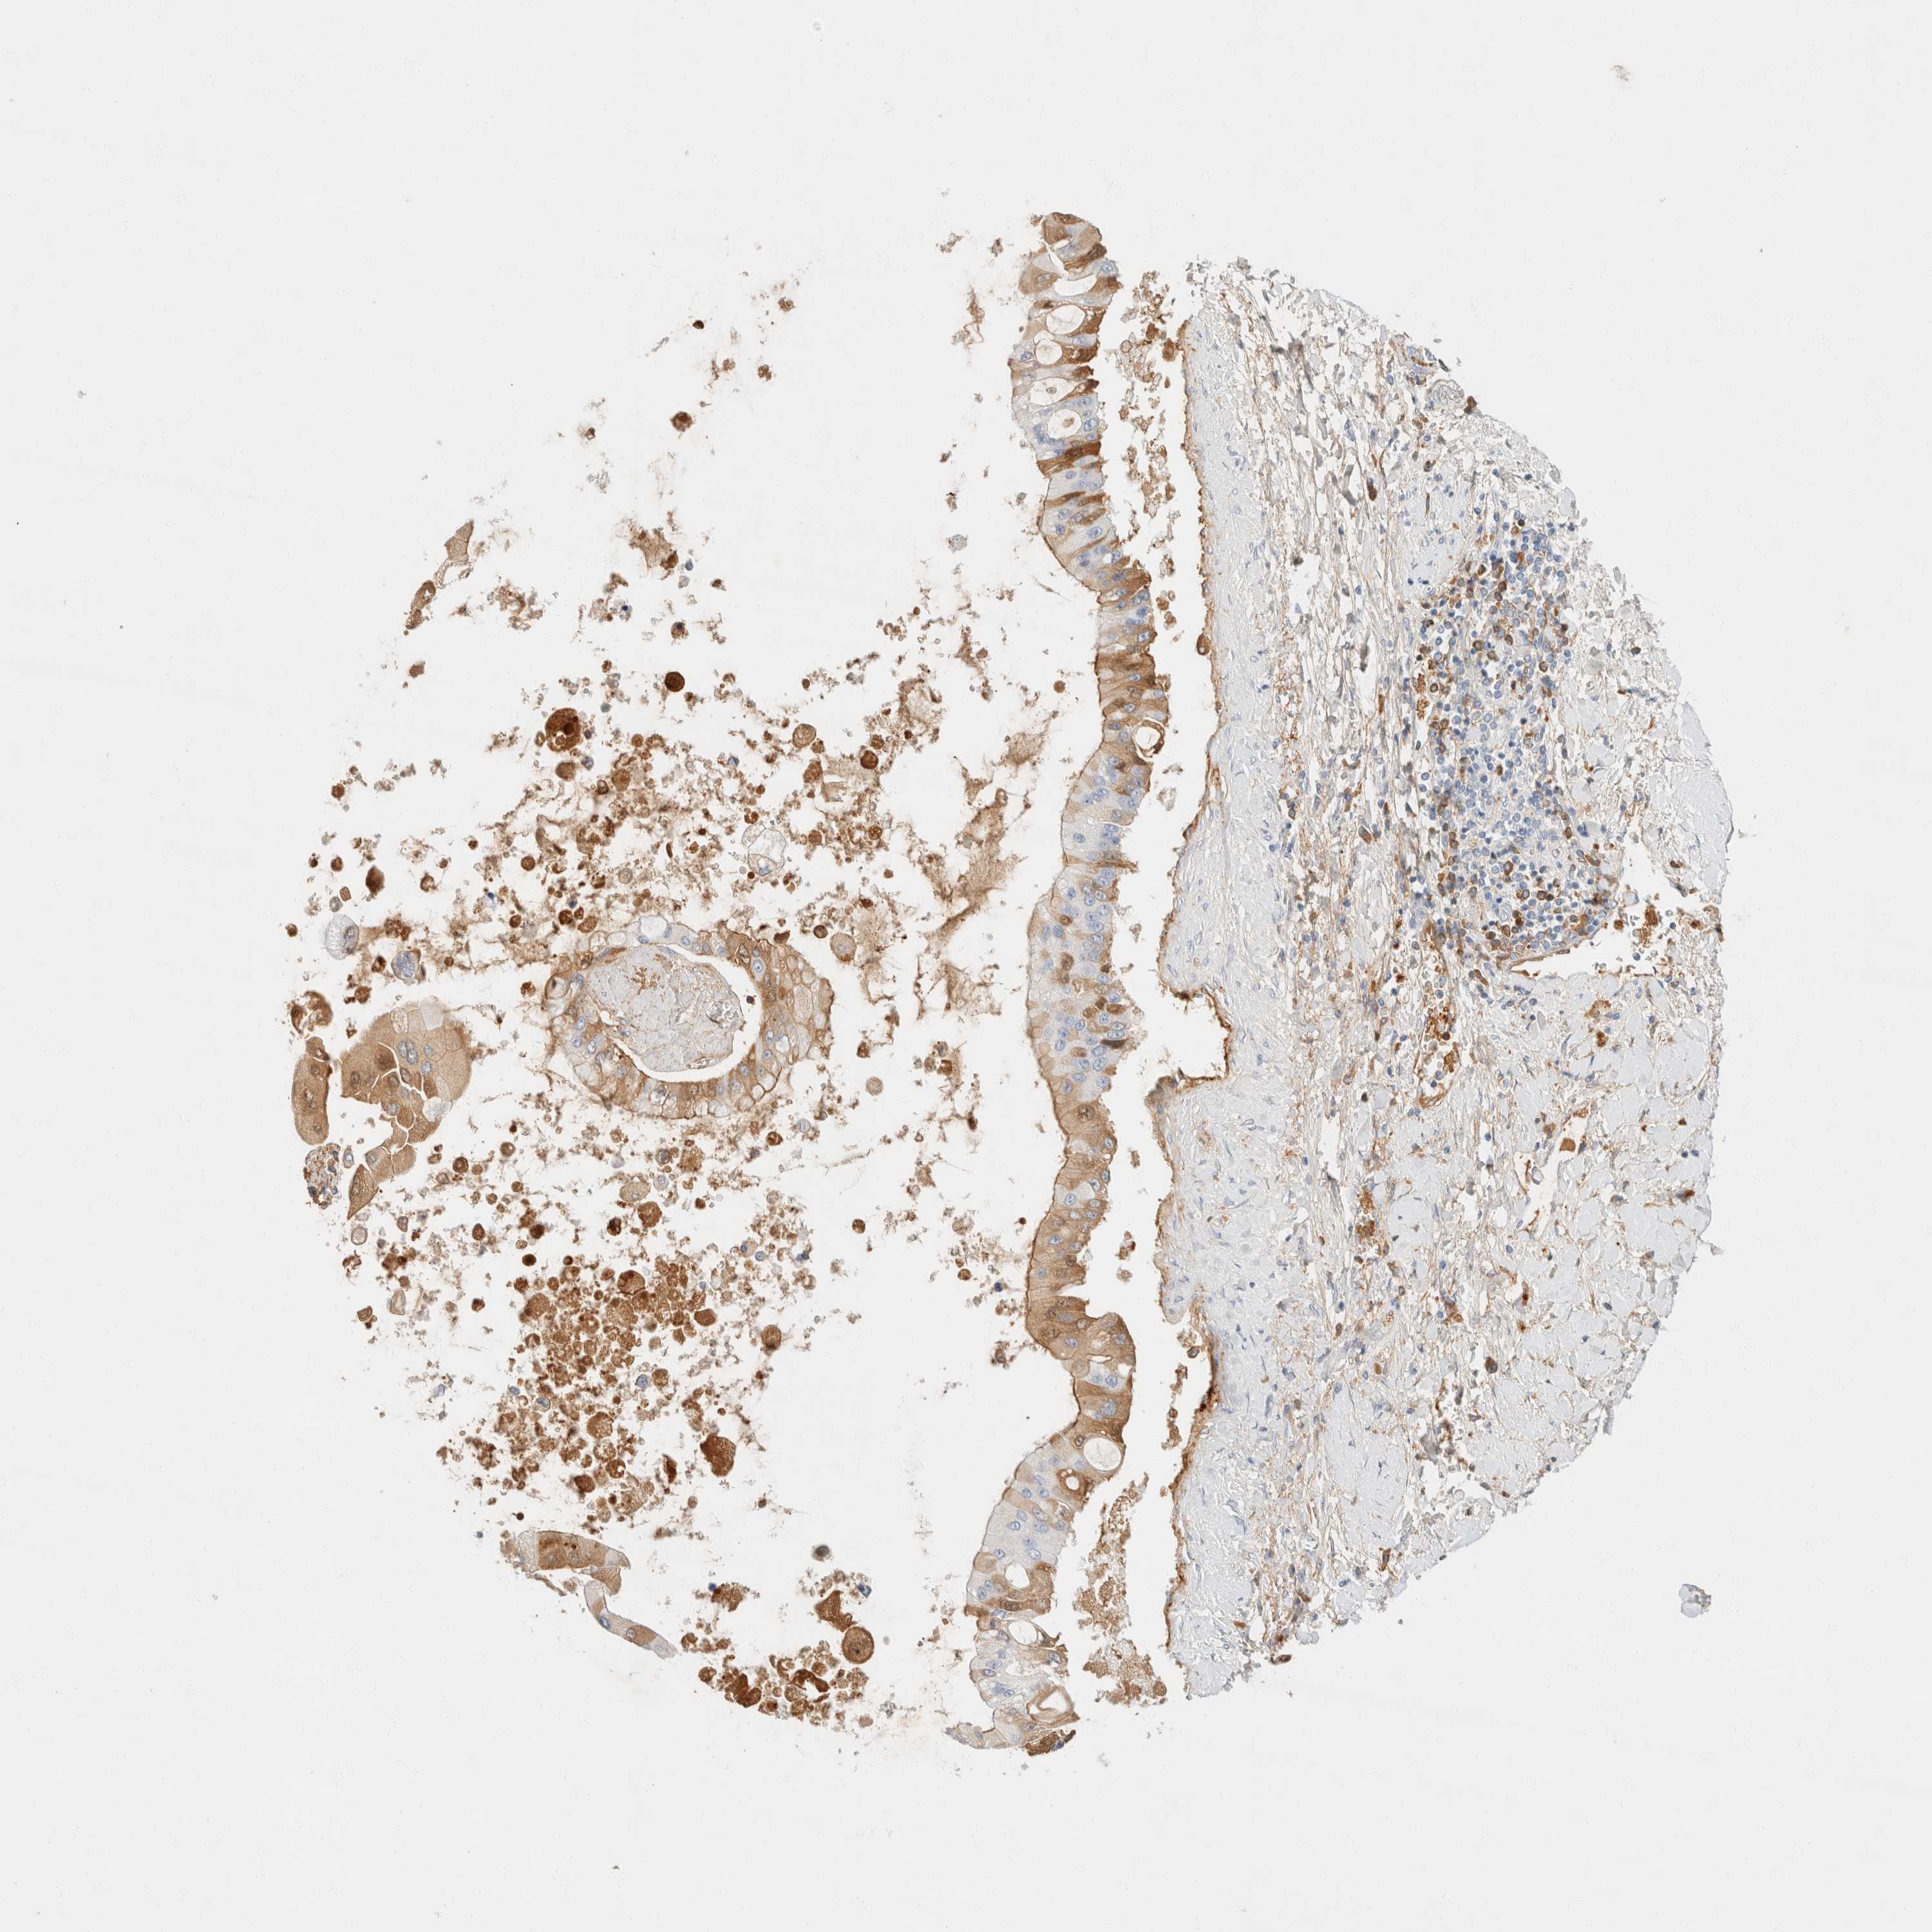

LIVER CANCER - Protein expressioni

A mouse-over function shows sample information and annotation data. Click on an image to view it in a full screen mode. Samples can be filtered based on level of antibody staining by selecting one or several of the following categories: high, medium, low and not detected. The assay and annotation is described here.

Note that samples used for immunohistochemistry by the Human Protein Atlas do not correspond to samples in the TCGA dataset.

Antibody stainingi

Antibody staining in the annotated cell types in the current human tissue is reported as not detected, low, medium, or high, based on conventional immunohistochemistry profiling in selected tissues. This score is based on the combination of the staining intensity and fraction of stained cells.

Each image is clickable and will lead to virtual microscopy that enables deeper exploration of all samples and also displays staining intensity scores, fraction scores and subcellular localization as well as patient and tissue information for each sample.

Antibody HPA023694

Staining

High

Medium

Low

Not detected

Intensity

Strong

Moderate

Weak

Negative

Quantity

>75%

75%-25%

<25%

None

Location

Nuclear

Cytoplasmic/membranous

Cytoplasmic/membranous,nuclear

Cholangiocarcinoma

Carcinoma, Hepatocellular, NOS